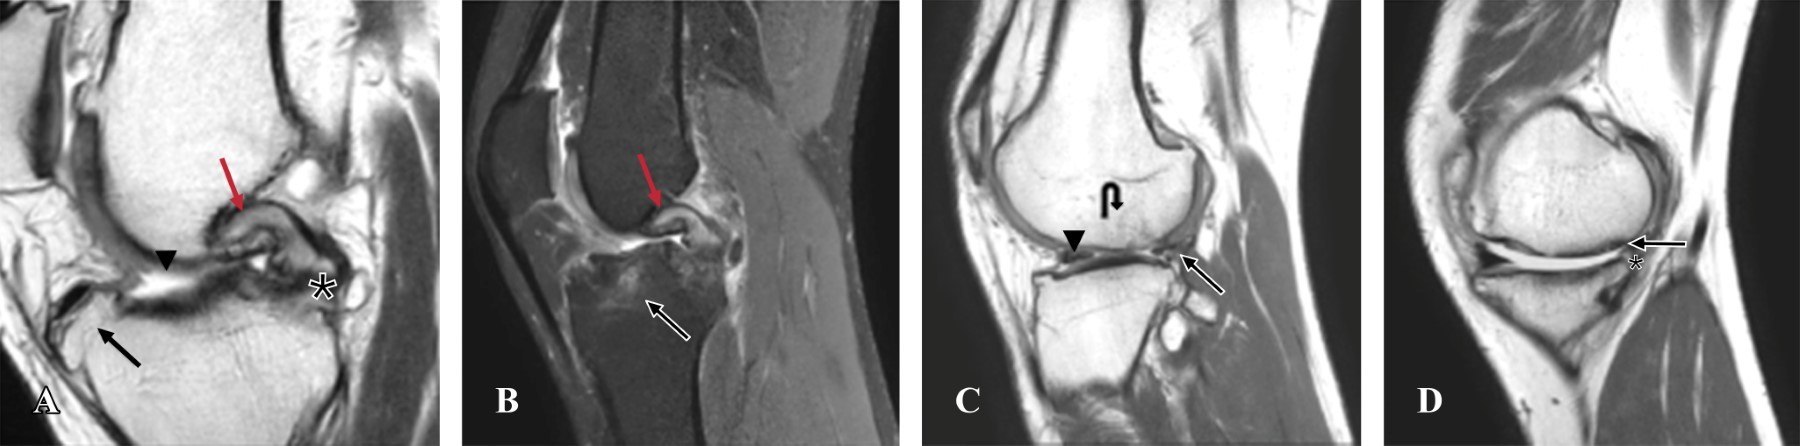

A la exploración física se evidencia dolor a la palpación sobre línea articular lateral y superficie anterior de la rodilla; arcos de movilidad de rodilla con flexión activa de 85°, flexión pasiva de 100°, extensión completa. Fuerza por grupos musculares de rodilla 5/5 con dolor referido a cara anterior de la rodilla. En las maniobras especiales para evaluar clínicamente la articulación de la rodilla se evidencian cajón anterior, Lachman, Lelli's: positivos; McMurray, Steinman y Apley lateral y medial: positivos. Se solicita resonancia magnética simple de rodilla derecha, se encuentra: ausencia de LCA, osteoartrosis grado III-IV del compartimento femorotibial medial, osteoartrosis grado II del compartimento femorotibial lateral, adelgazamiento de asta posterior y cuerpo de menisco lateral con mínima porción residual, desgarro horizontal de asta posterior y cuerpo de menisco medial, edema de ligamento cruzado posterior (LCP) con cambio de la degeneración mucoide (Figuras 1 y 2). Se realizaron mediciones radiográficas para notch intercondíleo y ángulo alfa, en corte axial y sagital, respectivamente (Figura 3).

El ángulo alfa se mide con el eje diafisario del fémur y la línea de Blumensaat en resonancia magnética sagital y el notch intercondilar femoral en resonancia magnética en corte axial en la zona de mayor profundidad del hueco poplíteo. En un estudio de casos y controles, Barnum M y colaboradores definieron que el valor del ángulo alfa fue de 41.6° en hombres y 40.5° en mujeres en los controles. Se observó que un ángulo alfa aumentado y un tipo A del notch se relacionaban con mayor número de lesiones de LCA. Cada grado de aumento del ángulo alfa incrementa la probabilidad de lesión del LCA en 67 y 119%; así como el tipo A del notch aumenta 399% y 450% el riesgo de lesión en mujeres y hombres, respectivamente. Concluyeron que un ángulo alfa aumentado resulta en un pinzamiento del LCA en el notch intercondilar anterior e incrementa la probabilidad de lesionarse el LCA.7 Con base en las características clínicas e imagenológicas de nuestro paciente y como demuestra Barnum en su estudio, la probabilidad de lesión del LCA en nuestro paciente es alta debido a que tiene un ángulo alfa 4° por encima del valor normal reportado en la literatura, lo que aumenta su riesgo de lesión en aproximadamente 400%; esto, añadido a las lesiones sobreagregadas que presenta nuestro paciente y al grado de artrosis, favorece a una falla en la reconstrucción del LCA.